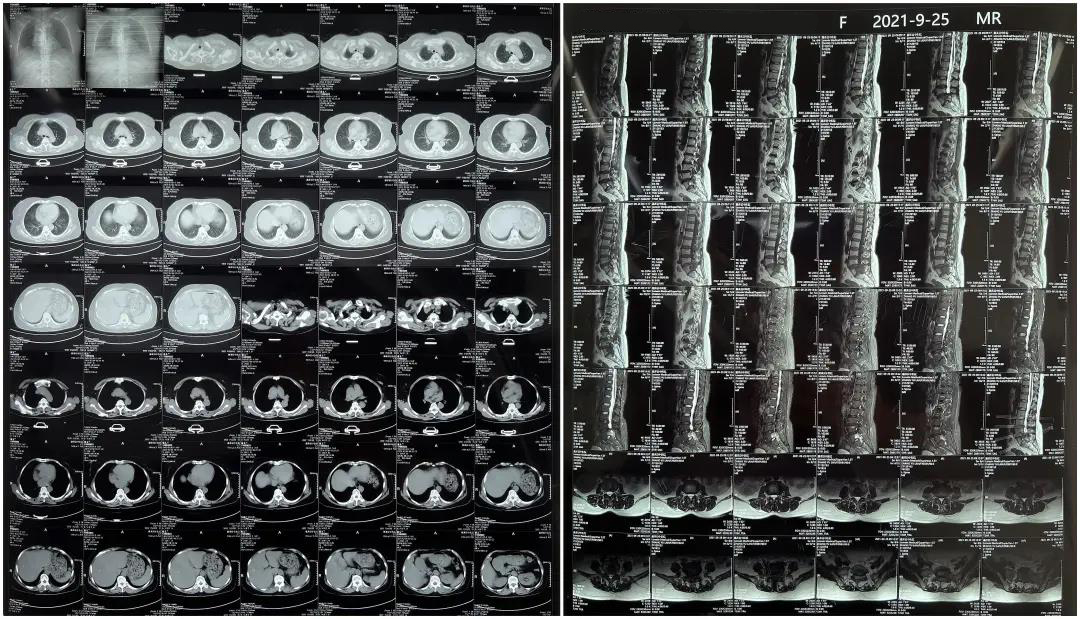

患者下腰部疼痛,活動受限,伴有左下肢疼痛5年,久站或彎腰干活時疼痛加劇,臥床休息后疼痛癥狀緩解,近一個月情況加重,需行椎板減壓+釘棒固定術。

術前患者核磁共振圖像

顯示L3/4、L4/5椎間盤突出,L5-S1水平椎管內占位